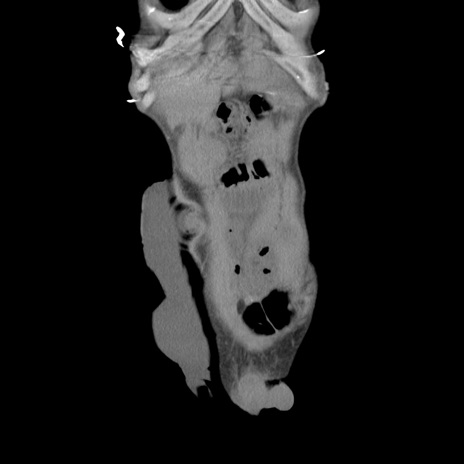

症例11(冠状断像)